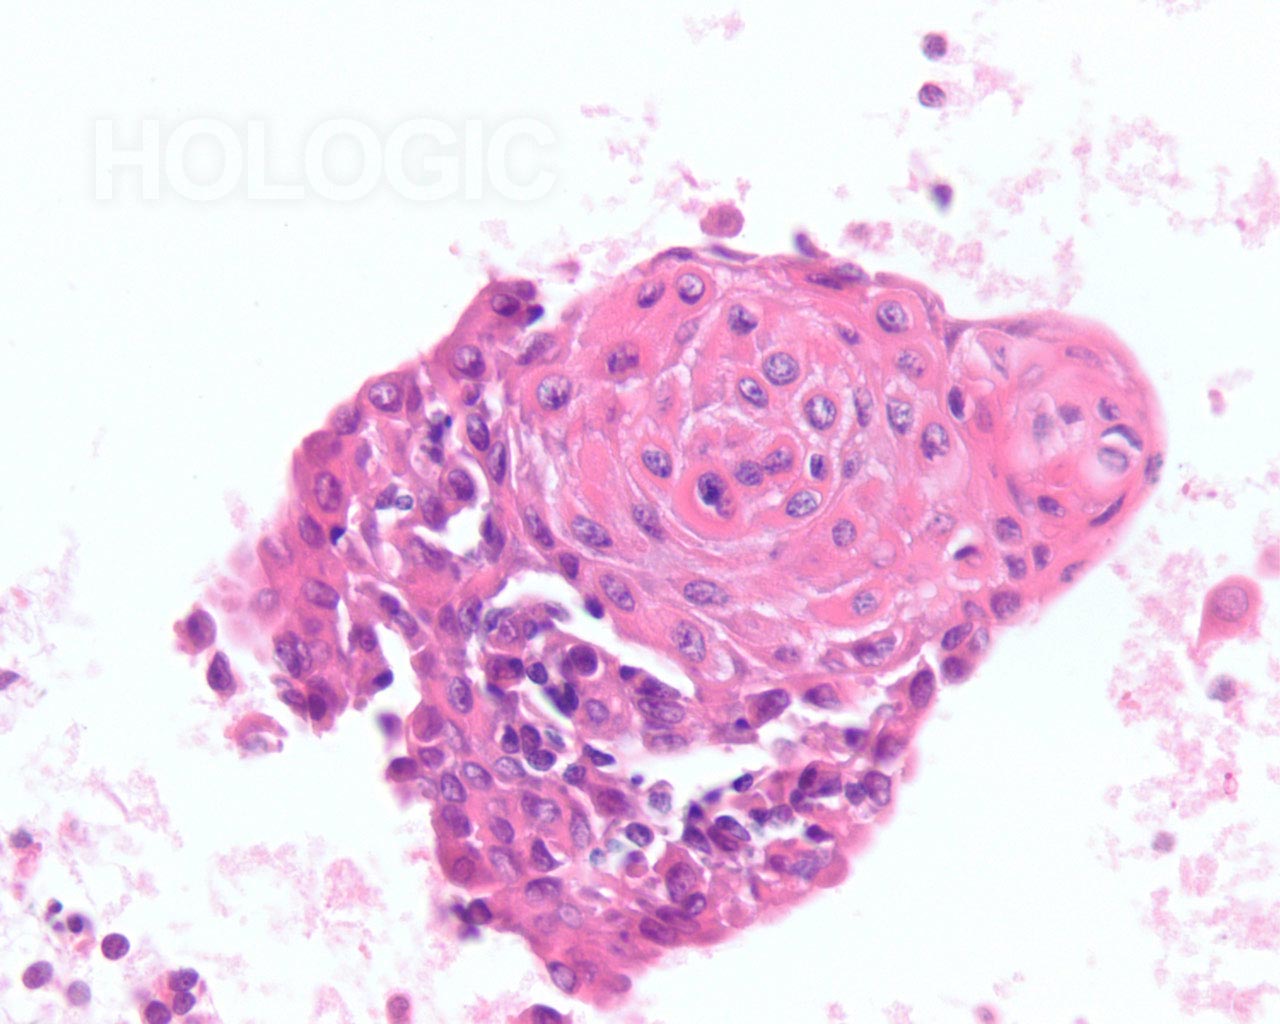

Met celblokken kan de afmeting van de follikel beoordeeld worden op een manier die een aanvulling vormt op de ThinPrep-glaasjes. Om een follikel als groot aan te merken, moeten de folliculaire cellen over een tamelijke grote afstand 2-dimensionaal georganiseerd zijn; als de follikels klein zijn, bevinden de cellen zich niet in een brede 2-dimensionale, platte laag. Het is verrassend moeilijk het eens te worden over de definitie van ‘macrofolliculair’ [9]. Acht tot 10 folliculaire celdiameters lijkt een redelijke definitie voor de macrofolliculaire colloïd fragmenten [9], of voor de diameter van platte, 2-dimensionele macrofolliculaire lagen. In weefselcoupes die loodrecht op een macrofolliculaire groep zijn gesneden, zien de macrofollikels eruit als een lineaire ordening van ten minste 8 folliculaire cellen. Als de sectie in het vlak van een macrofolliculaire groep snijdt, kan men gemakkelijk een solide uitziende celmassa tegenkomen die analoog is aan een weefselcoupe die tangentieel recht door de ductale cellaag snijdt in een schildklier biopsie. Net als pathologen een dergelijke tangentiële coupe kunnen herkennen en kunnen onderscheiden van ductale hyperplasie, kan men een tangentiële coupe door macrofolliculaire groepen herkennen. Dit wordt hieronder geïllustreerd. Microfollikels hebben per definitie een hoge ratio tussen de cellen en het colloïd en de cellen kunnen niet in een brede 2-dimensionele laag liggen. In celblokcoupes vertonen microfollikels geen lange lineaire organisatie van cellen. Renshaw et al. vonden een significante grijze zone onder experts in het onderscheid tussen microfolliculaire en macrofolliculaire groeperingen op cytologische preparaten [9].Een van de belangrijkste grijze gebieden betreft het probleem van folliculaire cellen die artefactueel op elkaar zijn gestapeld. Deze artefactuele stapeling van cellen lijkt gemakkelijker te diagnosticeren in weefselcoupes. Een ander probleemgebied betreft die gevallen waarin microfollikels en macrofollikels door elkaar zijn gemengd. Het is ons en anderen opgevallen dat benigne stromanodulen vaak plat cytoplasma vertonen in de cellen van de microfollikels. De robuustere cellen van een folliculair neoplasma tonen vaak veelal kubusvormige of zelfs cilindrische, folliculaire cellen die de microfollikels bekleden [7]. Deze kenmerken zijn duidelijk in celblokcoupes en worden hieronder geïllustreerd.

Benigne folliculaire nodulen vertonen vaak een bijmenging van cytologisch verschillende typen folliculaire cellen. De follikels van folliculaire neoplasmen zijn meestal uniform van aard. Hoewel het uiterlijk van de follikels in een cytologisch preparaat van groep tot groep kan worden vergeleken, kan deze benadering van het beoordelen van de klonaliteit soms moeilijk zijn. Het kan bijvoorbeeld onmogelijk zijn om te weten of de FNA-naald buiten het neoplasma monsters heeft genomen. Met celblokken kunnen de morfologische kenmerken van waarlijk aangrenzende follikels over een bereik van enkele honderden microns geëvalueerd worden, zoals hieronder geïllustreerd wordt.

Er zijn enkele verschillen in het uiterlijk tussen kernen in directe uitstrijken, ThinPrep® en celblokken. Een voordeel van celblokken is dat ze een gemeenschappelijk platform vormen dat kan worden gedeeld met chirurgische pathologen die de uiteindelijke diagnose stellen op basis van een biopsiemonster. We illustreren het nut van deze benadering voor de classificatie van FNA’s van problematische laesies met folliculair patroon met gedeeltelijk ontwikkelde nucleaire kenmerken van papillair schildkliercarcinoom [3].

Papillair schildkliercarcinoom is een gemakkelijke diagnose als de nucleaire kenmerken goed ontwikkeld zijn en het monster goed is gepreserveerd. De beste diagnostische kenmerken van papillair schildkliercarcinoom zijn fijn verdeeld chromatine en een onregelmatige nucleaire envelop[2]. Het is interessant dat papillair schildkliercarcinoom het eerste voorbeeld is van een kanker waarbij de diagnostische nucleaire kenmerken rechtstreeks gerelateerd zijn aan de genen die de kanker veroorzaken (besproken in [10]). Een reeks van verschillende onregelmatigheden van de nucleaire envelop kan aanwezig zijn [11]. De chromatine van een papillair schildkliercarcinoom is verdeeld in erg fijne deeltjes en aangezien een groot deel van de chromatine gelijkmatig aan de nucleaire envelop kleeft, heeft zelfs een kleine vouw als gevolg dat de chromatine in de nucleaire envelop er uitziet als een lineair aggregaat of een langwerpige groef. Vooral intranucleaire cytoplasmische inclusies zijn kenmerkend voor een papillair schildkliercarcinoom, maar deze kunnen ook worden aangetroffen bij medullaire schildkliercarcinoom. Deze intranucleaire cytoplasmische inclusie ziet eruit als een scherpe demarcatie die afkomstig is van het heterochromatine in de nucleaire envelop, waardoor het een duidelijke donkerpaarse begrenzing van het cytoplasma vormt. Intranucleaire cytoplasmische inclusies komen zelden voor bij folliculaire neoplasmen [2].

Folliculaire neoplasmen tonen in tegenstelling tot een papillair schildkliercarcinoom compacte aggregaten van heterochromatine. Het is onze ervaring dat de kern van een papillair carcinoom grofweg kan worden onderscheiden van kernen van folliculaire carcinomen, doordat papillaire schildkliercarcinomen vaak meer lineaire aggregaten chromatine vertonen (erg oppervlakkige vouwen van de nucleaire envelop) dan ronde of geklonterde chromatinemassa’s. Deze kenmerken worden hieronder geïllustreerd.